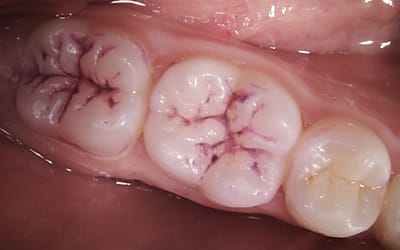

Preventing decay with fissure sealants

As a parent, you want the best for your child's health, and that includes their dental care. One of the most effective ways to help prevent cavities and maintain your child’s oral health is through...